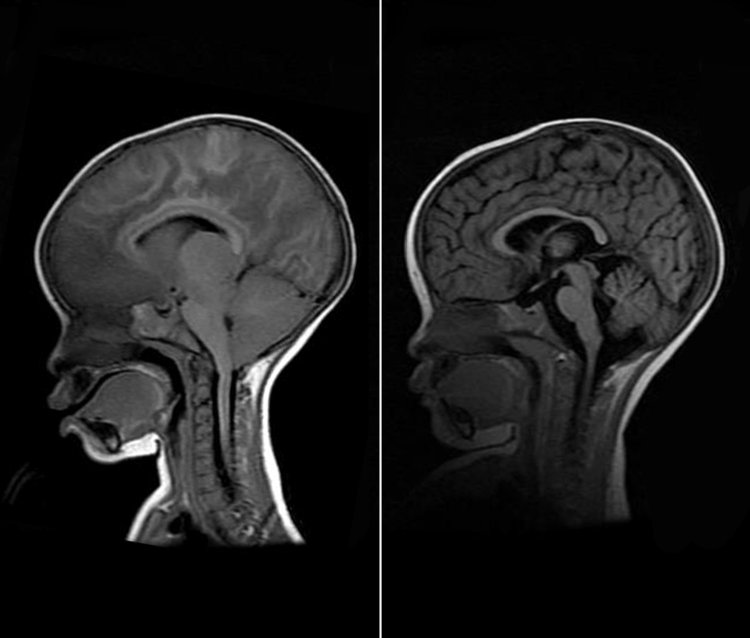

ବାହାରିଲା ବ୍ରେନ୍ ମ୍ୟାଲେରିଆ ଔଷଧ